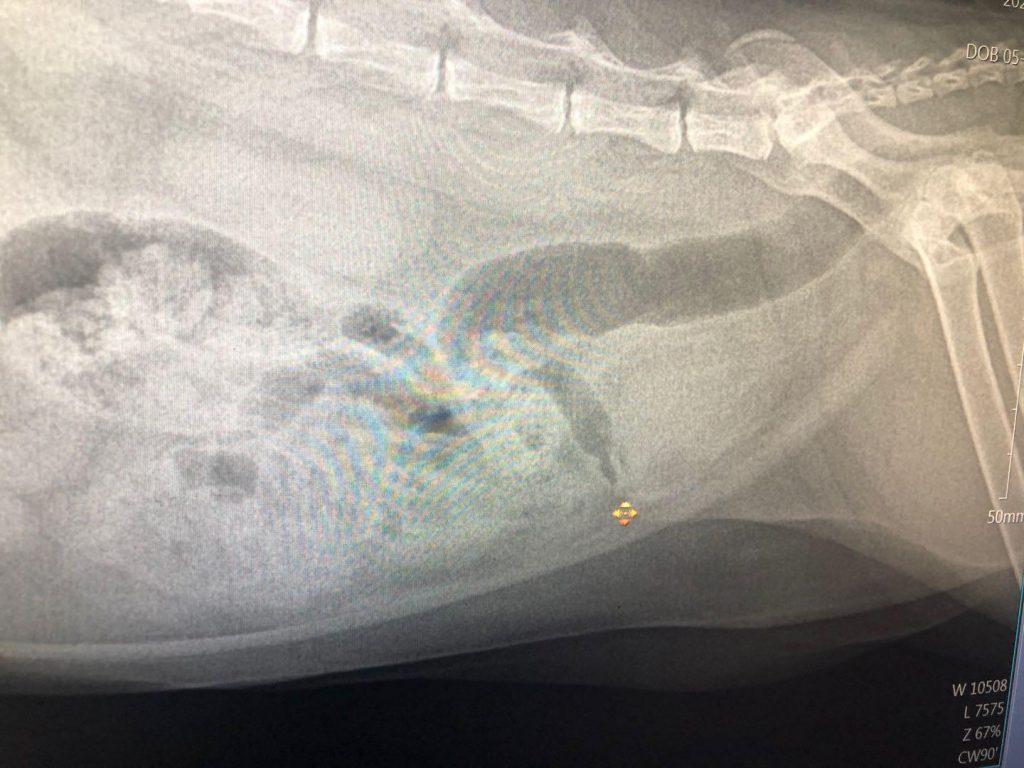

当主人突然发现猫咪泌尿系统又出现疾病,送往医院就诊时,医生会按照X光和B超接受大致了解判断,来判断猫咪现在的膀胱内部现状。如果没有是如果说尿中带血,轻微的膀胱炎,则会优先权采取的措施保守治疗,做很简单吊瓶处理,这个疗程,至少短短3天。猫咪的泌尿疾病你知道多少?猫咪尿血是真的血吗?(图9)可能会有的铲屎官有疑问:为什么不XX家的猫咪送医救治后要通过人工导尿或手术而不是先打点滴?这是而且,此时这只猫咪的肾脏压力膀胱压力太大了,如果没有此时打针输液,只会增加膀胱负担,而这样的状态下的猫又不能让其排尿,所以一定不能不能不能采取的措施输液治疗,第一时间一定会接受人工导尿。猫咪的泌尿疾病你知道多少?猫咪尿血是真的血吗?(图10)90%的人工导尿都会的很无惊无险,排尿最终后通过吃消炎药全面处理,大致7天之内就也可以出院手续了。只不过另外10%的猫咪,人工留置导尿也会一次,这时候就有必要参与毛石混凝土尿道改造治疗手术了,一旦到了这样的阶段:就那样的话一笔激亢的手术费用,因此,有当然失败的可能的风险,也会有可能留下后遗症。所以我,有些对猫咪生活冷淡不仔细的主人,若是出现情况,很多人就选择类型彻底放弃了。况且:唯一关心猫咪的主人,是不太可能让猫咪的病情发展到这一步的。猫咪的泌尿疾病你知道多少?猫咪尿血是真的血吗?(图11)猫咪的泌尿疾病,会很难从根本上绝对不能出现不可能发生,因此我们要尽很有可能会降低它的该病概率。